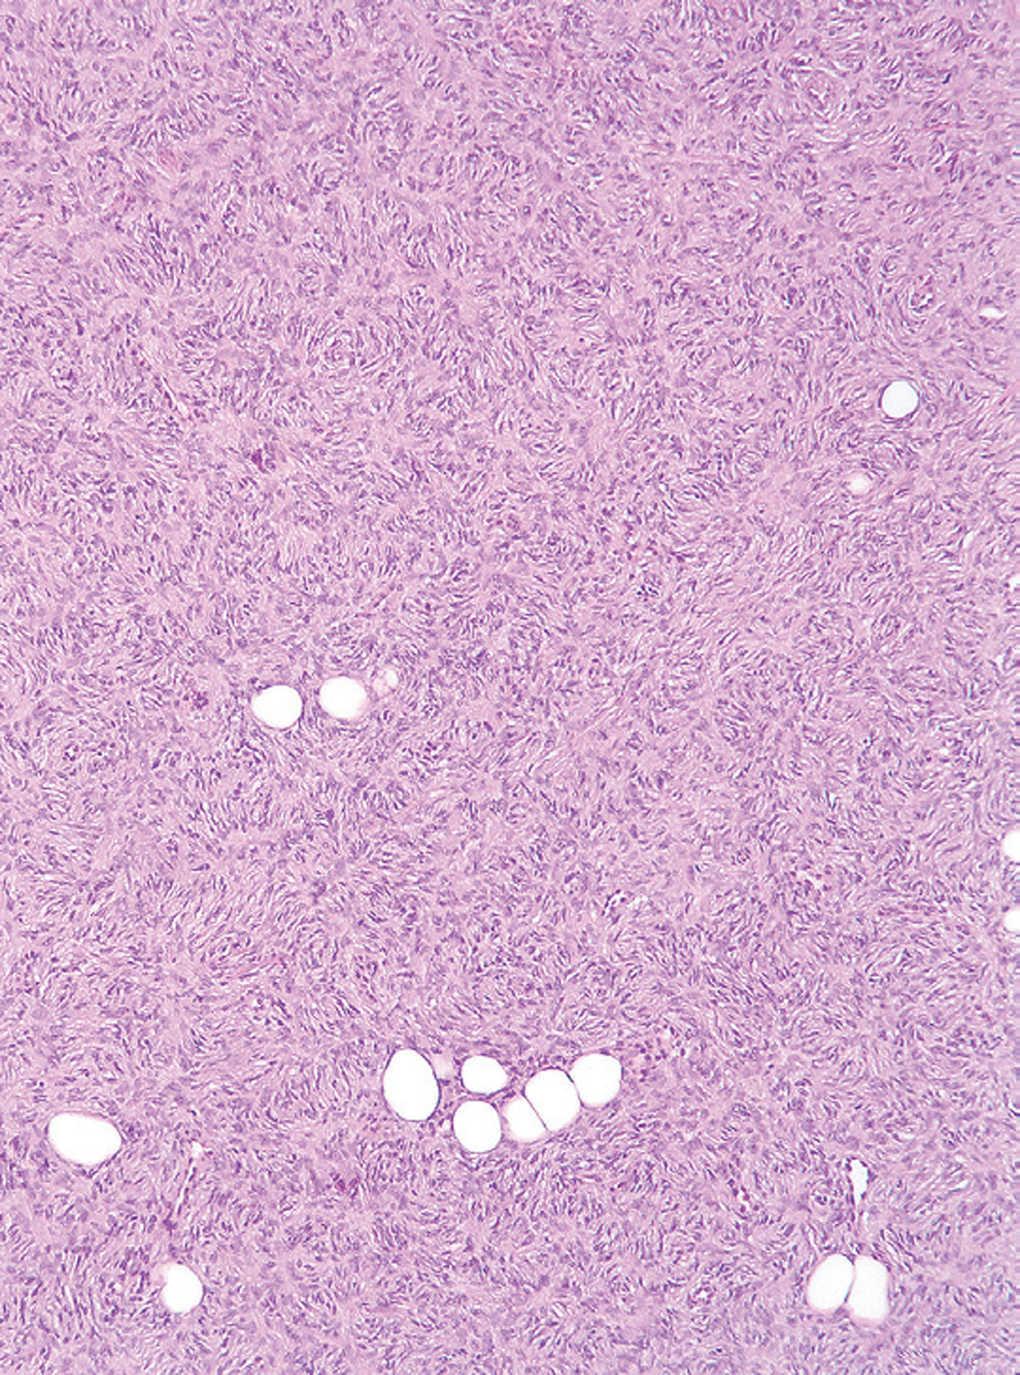

Se realizó biopsia cutánea en el extremo inferior de la placa para estudio histológico (figs. 2-4).

Fig. 3.--Detalle de la figura 2.

El estudio histopatológico mostró en la dermis profunda una densa proliferación de células fusiformes con núcleos abombados, levemente pleomórficos. Éstas estaban dispuestas en haces entrelazados con un patrón arremolinado en torno a un eje central constituido fundamentalmente por colágeno y alcanzaban el tejido celular subcutáneo.

La apariencia histopatológica típica del DFSP consiste en una densa proliferación de células fusiformes con núcleo abombado, dispuestas en haces arremolinados en un patrón estoriforme denominado en rueda de carro, alrededor de áreas acelulares centrales de tejido colágeno 4. Desde esta zona parten radialmente fascículos de células neoplásicas que invaden el tejido adiposo subcutáneo desde la dermis profunda, ya sea dejando islotes de adipocitos entre los fragmentos del tumor (patrón en panal de abejas, 30 % de los casos), ya sea en bandas paralelas a la epidermis (patrón en hojaldre, 60 % de los casos). Las células muestran grandes núcleos ligeramente pleomórficos, con escasas figuras mitóticas. En su periferia, el tumor tiende a crecer emitiendo prolongaciones mal delimitadas, lo que explica la dificultad clínica e histológica para determinar sus límites y la elevada tasa de recurrencia tras la extirpación quirúrgica convencional 8. El DFSP muestra positividad para CD34 y negatividad para factor XIIIa y proteína S-100, de gran valor para el diagnóstico diferencial con otros tumores.